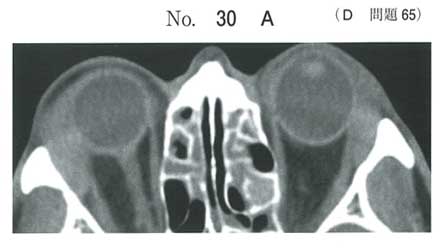

眼窩CTでは両眼窩上耳側の涙腺腫脹がみられ、いわゆるMikulicz病です。

ですのでIgG4関連疾患を念頭に置いて精査することになります。

なのでb、cはIgG4関連疾患の診断基準上、正解となります。

IgG4関連疾患と言えば自己免疫性膵炎ですが・・・